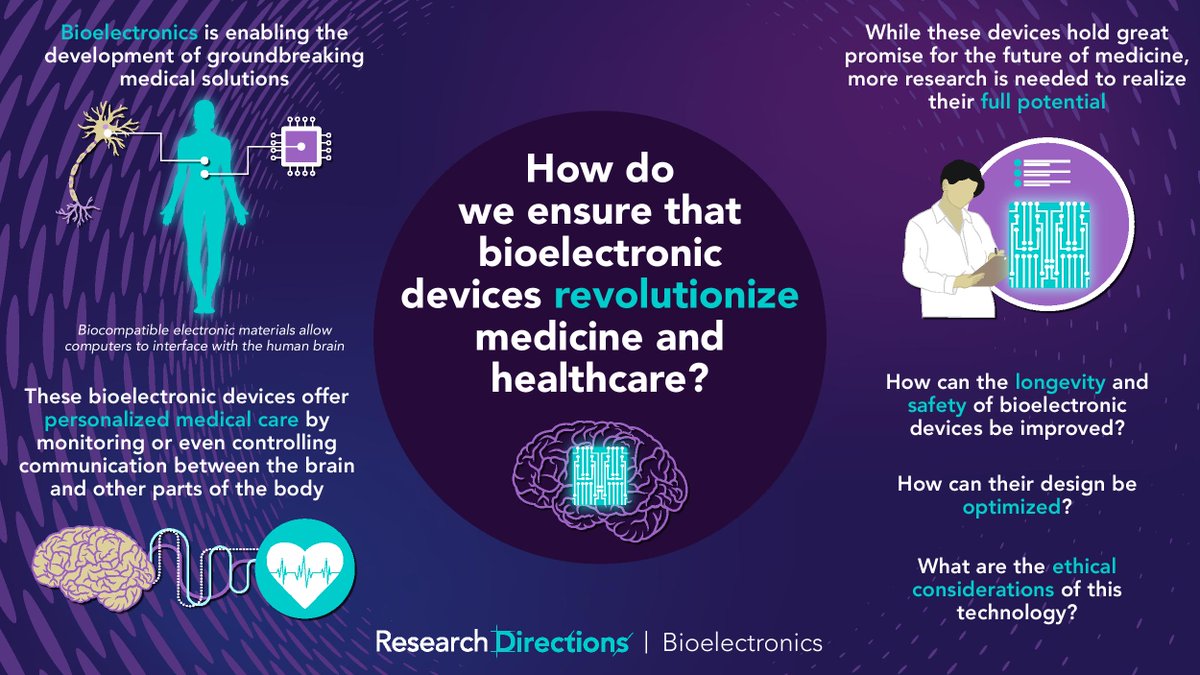

#RDBioelectronics welcomes contributions from researchers to answer this question from @sc_laboratories: 🟣How do we ensure that #bioelectronic devices revolutionize medicine and healthcare? Learn more about this question and how to contribute:cup.org/3pcKJ4o #bionics